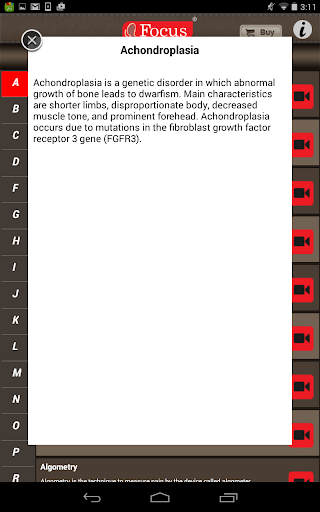

The FOCUS Animated Pocket Dictionary of RHEUMATOLOGY is the first ever animated dictionary in the subject. A valuable reference for physicians and students alike, it covers 100 rheumatology related terms and definitions. All the definitions have been graphically described with the help of 3D animations and are accompanied by text definitions.

The Focus Animated Pocket Dictionaries are the world’s first ever animated dictionaries that provide definitions of medical terms with the aid of realistic and narrated 3D animations, complimented with text definitions. Terms arranged alphabetically making definitions easy to search. These unique visual dictionaries are excellent reference sources for health professionals, students and health consumers. The videos play independent of the internet once downloaded.